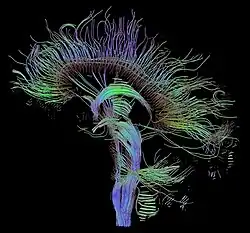

Magnetic resonance imaging (MRI) is a common form of biological data visualization used to form pictures of internal biological processes. Different settings of radiofrequency pulses and gradients result in different image appearances; these combinations are known as MRI sequences. A particularly notable subset of MRI is magnetic resonance angiography, which is a group of techniques used to image arteries and veins. MRI's imaging utility is further expanded upon by diffusion MRI and functional MRI, which can be used to capture neuronal tracts and blood flow respectively.

Diffusion MRI further relies on diffusion tensor imaging (DTI), which measures water molecule diffusion and directionality, and diffusion basis spectrum imaging (DBSI), which extracts multiple anisotropic and isotropic diffusion tensors.[39][40] Functional MRI relies on blood-oxygen-level dependent (BOLD) contrast, which measures the proportion of oxygenated hemoglobin in specific areas of the brain; this allows it to measure and model brain activity based on blood flow.[41] Further MRI techniques include saturation pulses (used to reduce motion artifacts), gradient echo (such as dynamic contrast enhancement), spin echo, and diffusion weighting (a signal contrast generation method based on differences in Brownian motion).[42][43][44]